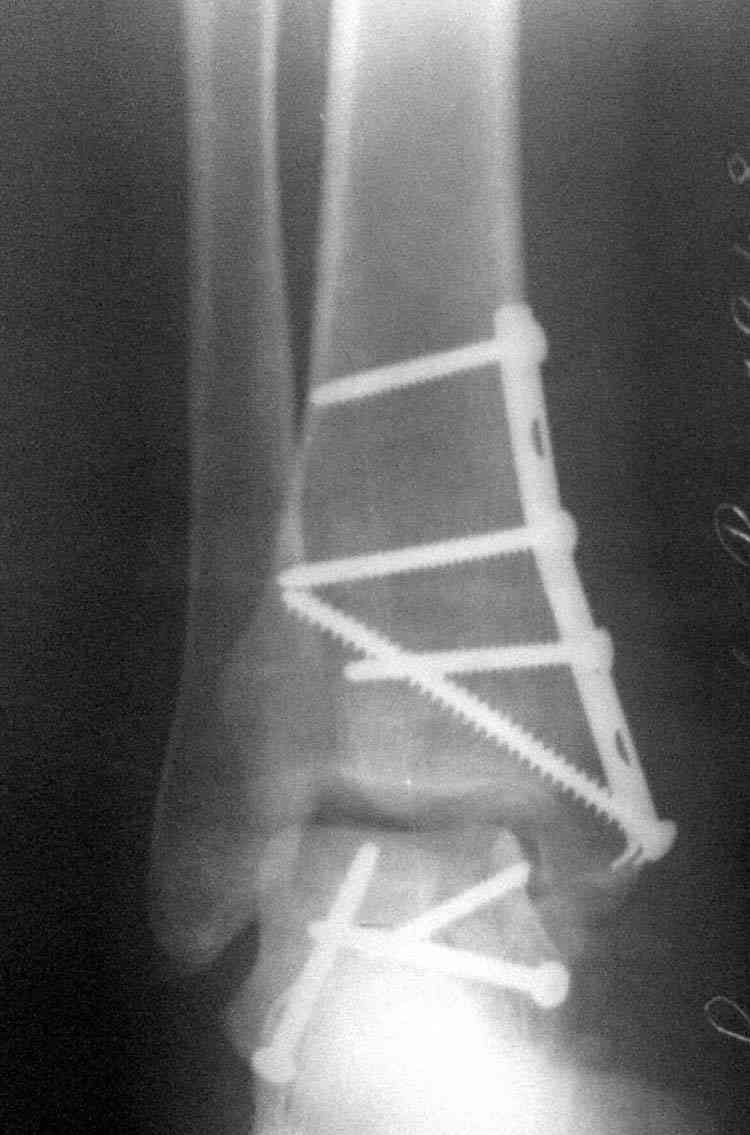

Случай с множественным оскольчатым переломом тарана оперированный из двойного доступа.

Через 14 мес.:

И второй случай из недавней ташкентской практики, (извините за качество ренгенограммы и только в одной проекции) случай падения с высоты (кстати моего друга - известного киноактера) - открытый

смещенный перелом тарана, с переломом переднего края дистального эпиметафиза большеберцовой кости.

При поступлении в приемной сделана первичная обработка с ушиванием открытой латеральной раны и вытяжением за пятку.

Из-за отсутствия времени пришлось оперировать на второе утро, из материала, что имеем на месте, фиксирован двумя шурупами, а третий-это контур сломанного жойстика в 4 мм. На дистальный медиальный конец тибиа antiglide 3.5 мм пластина. Через пару дней выписан и несмотря на предупреждение, самостоятельно начал нагрузку в 4 недели, время не ждет, снимается в боевике в Росийской Федерации.